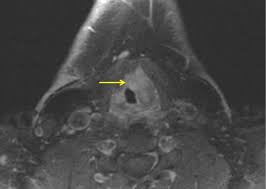

What Can Mimic Throat Cancer : 5 Vague Cancer Signs You Should Never Ignore Health Essentials From Cleveland Clinic : Throat cancer describes cancer of the voice box, the vocal cords, and other parts of the throat, such as the tonsils and the oropharynx.. Head and neck cancer develops from tissues in the mouth, larynx (throat), salivary glands, nose, sinuses or the skin of the face. Throat cancer and tongue cancer can be very dangerous types of cancer as they can block the ability to breathe and/or eat. Throat cancer causes, signs and symptoms. Throat cancer forms in the larynx (voice box) or pharynx (throat) and raises the risk of the patient developing another cancer later in life, particularly of the lungs, esophagus or larynx. Throat cancer refers cancer that develops in your throat (pharynx) or voice box (larynx).

The symptoms of head and neck cancers can mimic those for other conditions so it is important to see your physician for a proper diagnosis. Throat cancer forms in the larynx (voice box) or pharynx (throat) and raises the risk of the patient developing another cancer later in life, particularly of the lungs, esophagus or larynx. Throat cancer causes, signs and symptoms. During the entire time i had it, there was absolutely no pain or discomfort from it. However, it is quite difficult to identify throat cancer from an early stage of the disease. Many types of throat cancer begin as squamous cell carcinoma. What throat cancer look like. Learn the different symptoms also called: Mouth and throat cancers are cancers that originate on the lips, the roof, sides, or floor of the mouth, tongue, tonsils, or back of the throat. What can we help you find? It is divided into three major sections throat cancer can be discovered in the nonsmoker as well. The most common sign of throat cancer is a sore throat. Learn about the causes of throat cancer, including smoking and excess alcohol consumption.

The common early symptom is a persistent hoarse voice. Head and neck cancer can be hard to diagnose, because symptoms are often mild and can mimic less serious conditions such as a cold or sore throat. Throat cancer can develop in any part of the throat. Hypopharyngeal cancer, laryngeal cancer, laryngopharyngeal cancer, nasopharyngeal cancer, oropharyngeal cancer, pharyngeal cancer. Head and neck cancer develops from tissues in the mouth, larynx (throat), salivary glands, nose, sinuses or the skin of the face.